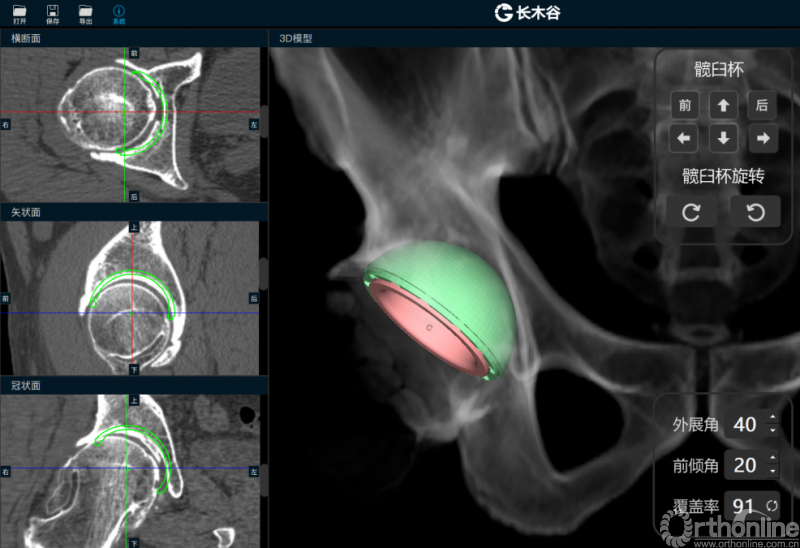

患者术前CT三维重建图像

由AI HIP系统对患者的髋关节CT数据进行人工智能分割与关键点识别,术者可根据智能分割与测量结果综合判断患者情况。如图可见,该患者关节内可见明显畸形。

AI HIP系统智能安放54mm直径的强生Pinnalce髋臼杯

最后,AI HIP系统根据患侧股骨颈干角、偏心距偏大的特殊情况,智能选择使用高偏高颈干角假体,对下肢等长和等偏心距重建做出了精准设计。根据系统预测结果,术中使用54mm Pinnalce髋臼杯、12号CORAIL高偏股骨柄、36mm 陶瓷股骨头、小转子上23mm截骨,实现髋关节的个体化、精准化重建。